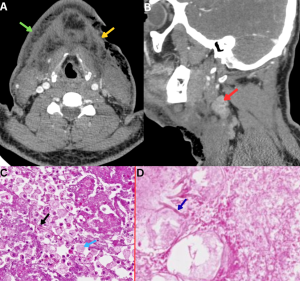

Fig 26: Clinical history:

A 49-year-old immunocompromised male presented with painful neck swelling and a non-healing ulcer over the lateral neck.

Figure A:

Axial contrast-enhanced CT (CECT) neck image demonstrates diffuse subcutaneous fat stranding (green arrow) with focal irregularity of the overlying skin and subcutaneous tissues (yellow arrow).

Figure B:

Sagittal CECT neck image demonstrates an enlarged, homogeneously enhancing cervical lymph node (red arrow).

Figure C:

Histopathology from the cutaneous ulcer demonstrates foamy macrophages (blue arrow) with broad, aseptate fungal hyphae showing right-angle branching (black arrow), consistent with mucormycosis.

Figure D:

Histopathology from the cervical lymph node demonstrates extensive necrosis with fungal hyphae (dark blue arrow), confirming nodal involvement.